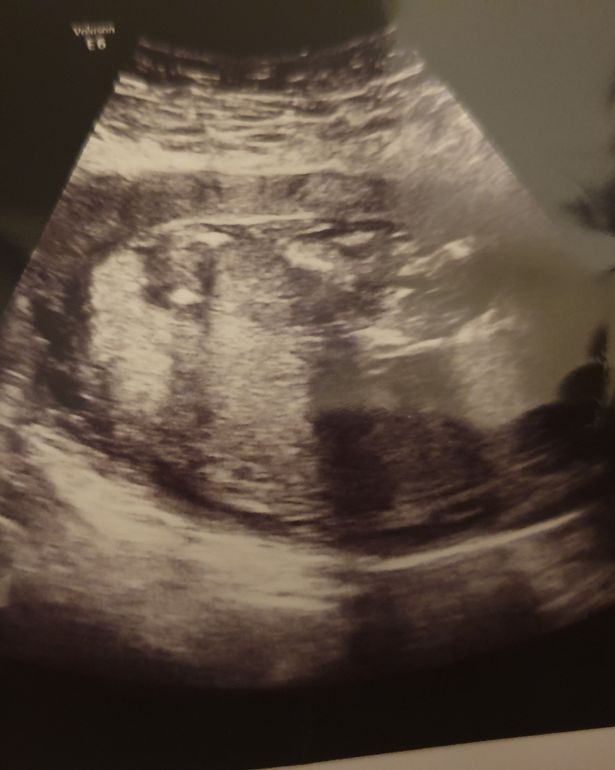

据《镜报》12月9日报道,英国德比郡一名女子怀孕仅13周羊水就破了,但是她坚持拒绝中止妊娠。在她怀孕29周后,她成功地生下了一名女婴。令人震惊的是,孩子奇迹般地活了下来,医生曾一度警告称,这个孩子会是个死胎。

23岁的柯斯蒂·米宗(Kirsty Mizon)在怀孕13周时羊水就破了。医生不断告诉柯斯蒂,孩子会胎死腹中。柯斯蒂甚至已经准备好了葬礼。然而,最终孩子顺利地出生了。